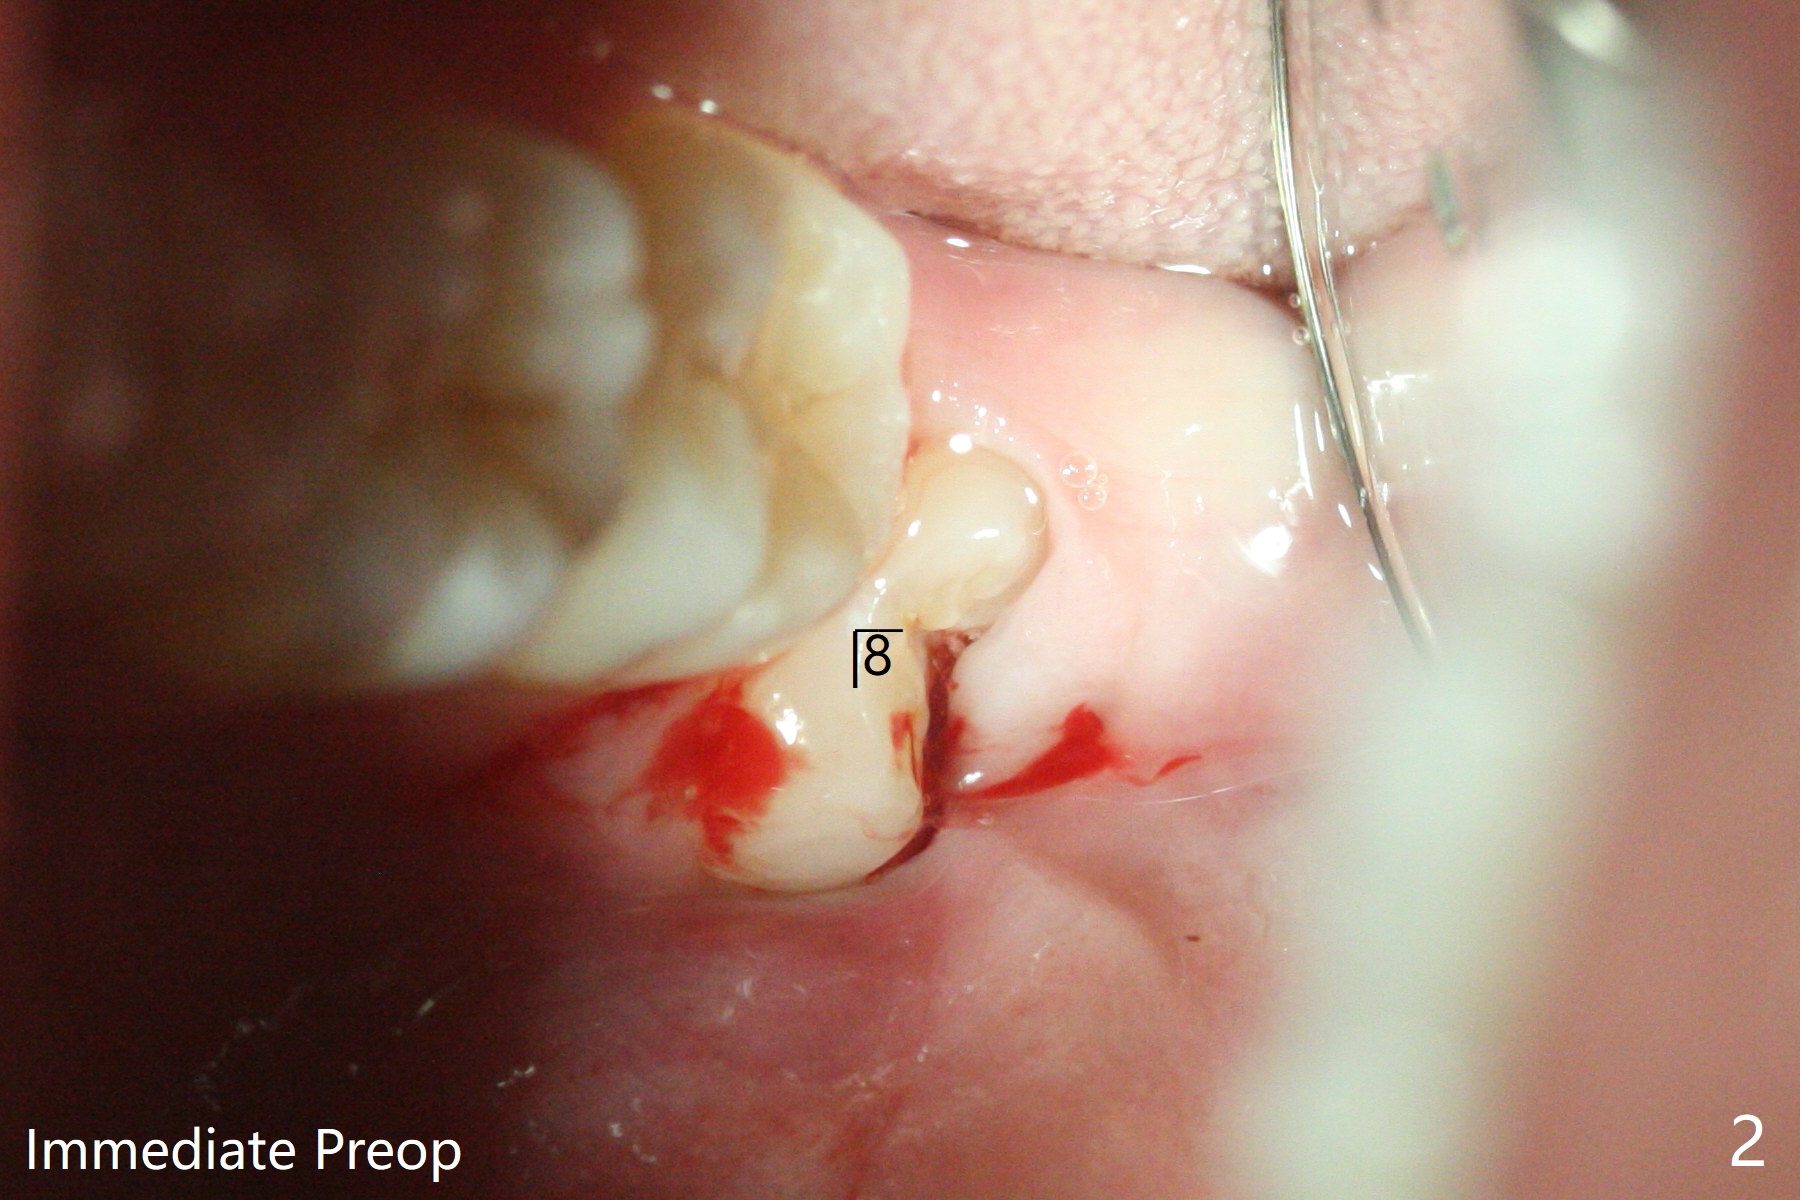

30岁男下颌深洗后,局部浸润麻醉,准备拔除颊侧阻生智齿(图一至三),每个牙槽窝放置0.5cc骨水泥(Bone Cement (Bond Apatite from Augma)),覆盖半块胶原塞,4-0铬羊肠线缝合(图四)。